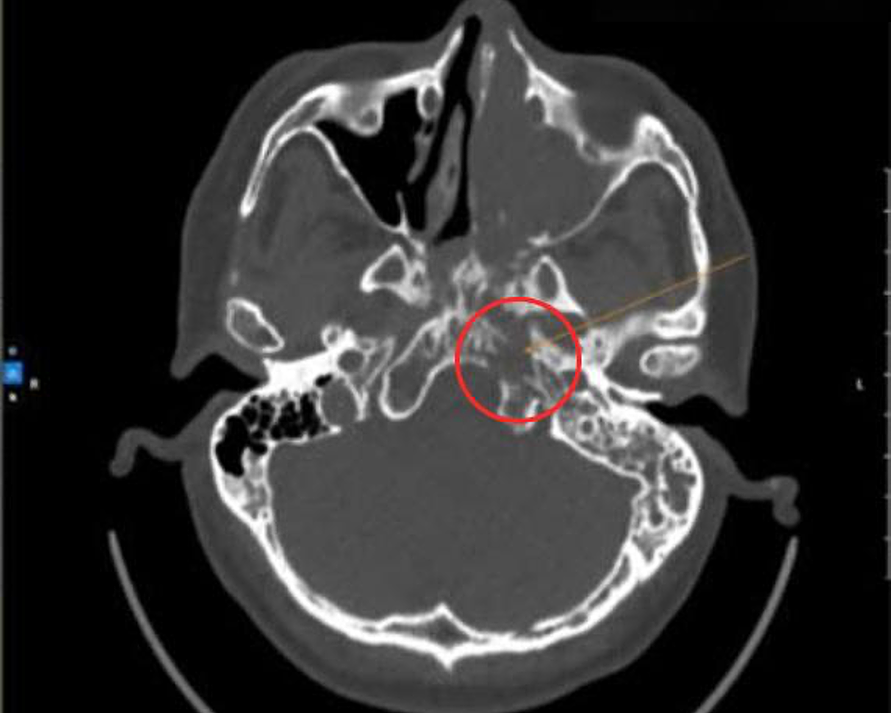

The nasal cavity tumor obscuring the patient's nasopharynx area on a CT scan. Photo: Tam Anh District 7 General Clinic |

Endoscopy results at Tam Anh District 7 General Clinic in Ho Chi Minh City revealed a tumor filling Mr. Lang's left nasal cavity. The mass obstructed his posterior choana and nasopharynx, causing bleeding. CT scans further showed the lesion had spread, filling the left ethmoid, frontal, and sphenoid sinuses, as well as both sides of the nasopharynx.

Master of Medicine, Doctor of First Degree Specialization Truong Tan Phat, Head of the Ear, Nose, and Throat Unit, stated that Mr. Lang had exudative rhinosinusitis. Due to suspicion of malignancy, a biopsy of the nasal cavity tumor was ordered. The biopsy confirmed nasal cavity cancer, specifically squamous cell carcinoma. Surgeons at the clinic subsequently removed the malignant tumor and the invaded bone.